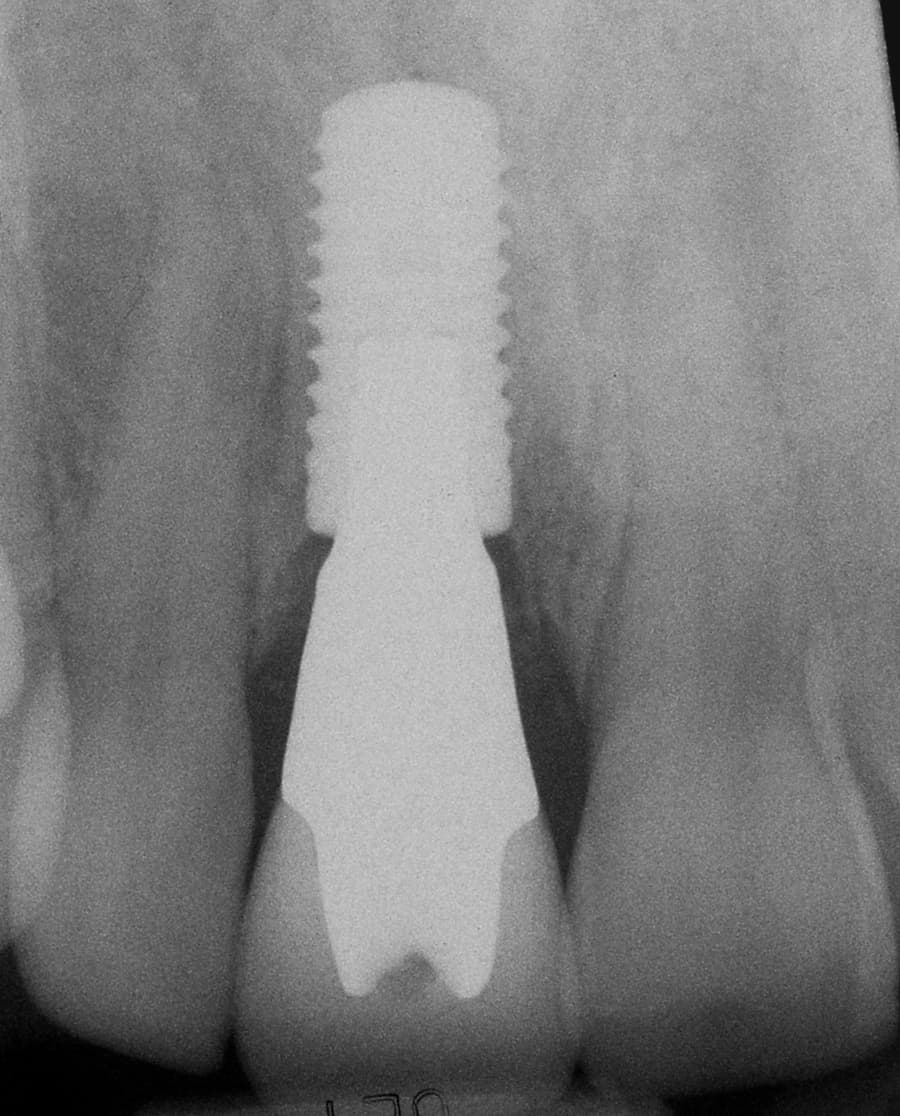

Immediate Implant Placement, Ceramic Implant Abutment, Ceramic Implant Crown

After: Single, all-ceramic crown attached to an all-ceramic, CAD-CAM designed and generated abutment (implant post). A delayed treatment approach was undertaken: tooth/root removal and grafting; 4 months healing; interim removable partial tooth replacement; implant placement; 6 months healing; proto-type (transitional fixed) implant crown, then the definitive implant restoration. The new tooth blends in perfectly with the natural, adjacent teeth.